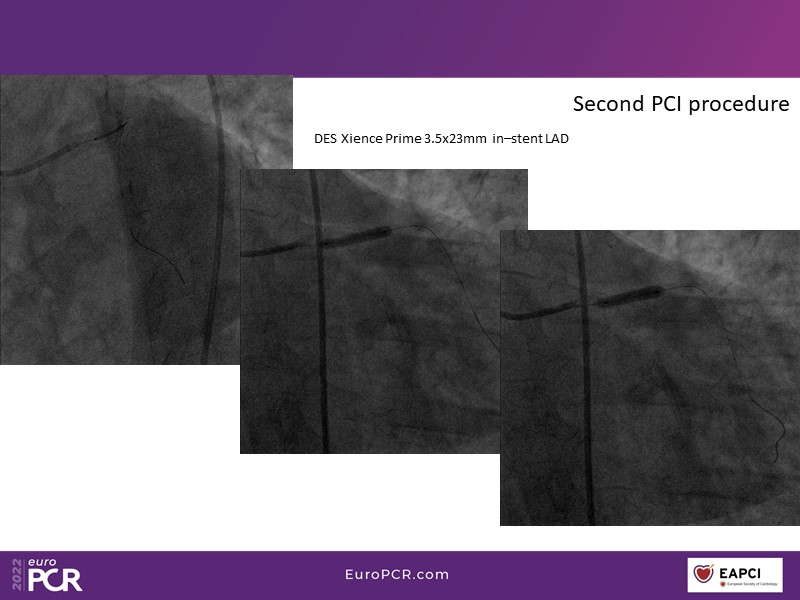

This EuroPCR 2022 session aims to show, based on real-life cases, that even complex coronary disease can be treated without the need for permanent coronary stents. Learn how to prepare the vessel, deliver the therapy, and assess immediate outcomes after "DCB-alone" PCI, discuss de novo, small vessels, and in-stent restenosis cases with follow-up, define what may be an optimal long-term result, refresh the scientific bases, and understand the clinical benefits and safety of paclitaxel DCBs.

- To know how to prepare the vessel, deliver the therapy and evaluate the immediate results after "DCB-alone" PCI

- To discuss de novo, small vessels and in-stent restenosis cases with follow-up and define what may be an optimal long-term result